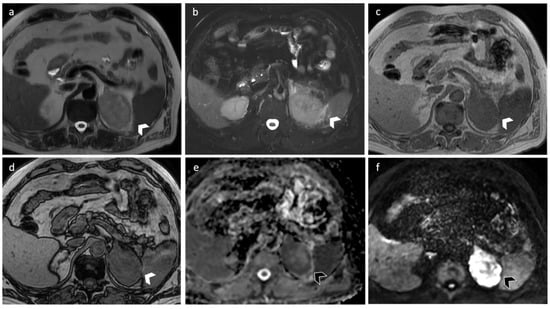

3.3. Carcinoma